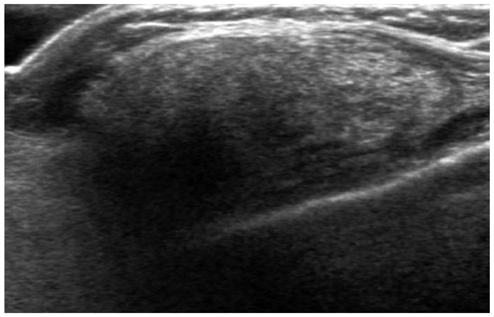

- The purpose of this study is to review various breast diseases in children and adolescents and to illustrate the sonographic findings. We reviewed the cases at our institution in order to identify breast disease in children and adolescent patients who underwent sonography and mammography. Breast disease in children and adolescents included developmental disturbance, infection, benign tumors and inherent defects. In contrast to adults, the radiologic findings of malignant breast conditions in pediatric populations have rarely been reported; however, we show ductal carcinoma in situ with juvenile fibroadenoma and rhabdomyosarcoma. During childhood and adolescence, the recognition and correct identification of physiologic breast development and specific lesions in breast entities on radiologic findings is most helpful in identifying and characterizing abnormalities and in guiding further investigation.